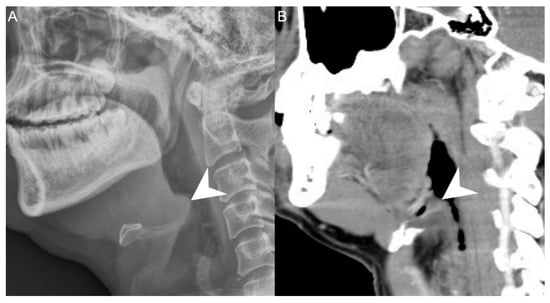

We retrospectively reviewed the medical records of 502 patients diagnosed with DNI who were admitted to Chang Gung Memorial Hospital in Linkou, Taiwan, between June 2016 and August 2021. DNI diagnosis was performed by ultrasonography (USA) and computed tomography (CT), while AE was diagnosed by a lateral neck X-ray (Figure 1), flexible fiberoptic laryngoscopy, and CT. The treatment course included antibiotics, US-guided needle drainage, and open surgical incision and drainage. The empirical antibiotics used were ceftriaxon 1 gm Q12h and metronidazole 500 mg Q8h, based on previous reports, to cover aerobic and anaerobic bacteria before the culture results were available [10,11].

Figure 1. A patient with concurrent acute epiglottitis and deep neck infection as seen from a (A) neck lateral view and (B) sagittal view on CT. Arrowhead: swelling of the epiglottis. 300 × 300 DPI.